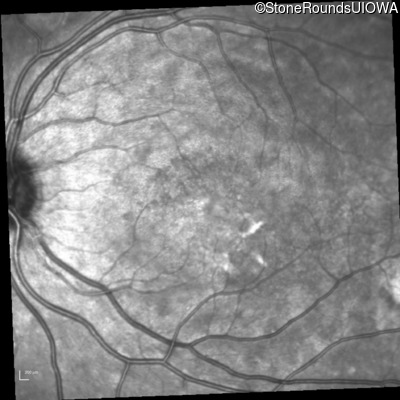

Infrared Fundus Photograph - Right - 20/100 sc

Exemplar

Infrared Fundus Photograph - Left - 20/25 -3 sc